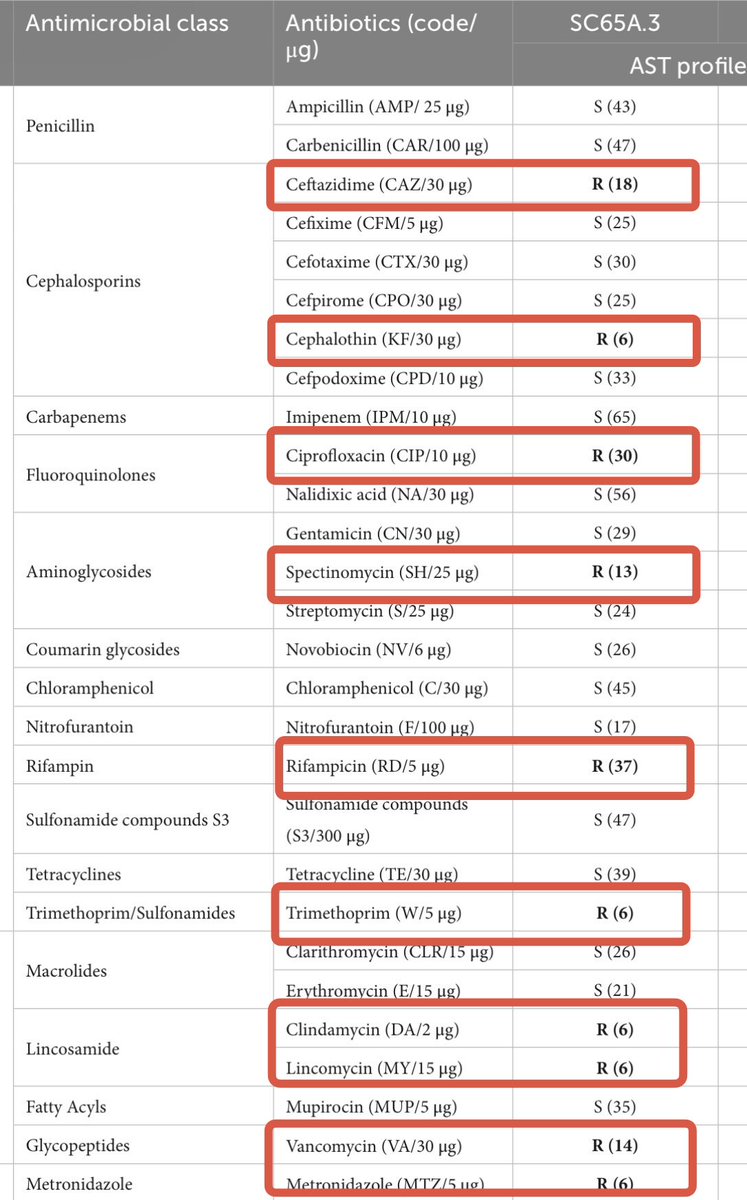

Si te dicen q un #NUEVO antibiótico NO TIENE RESISTENCIAS🆕💊…. no te lo creas! Frontiers - Microbiology bacteria congelada hace 5000 años🥶…ya era R a 10 ATB📸. Los ATB provienen de la naturaleza y existen mecanismos en ella para combatirlos Frontiers - Microbiology 🔗🆓frontiersin.org/journals/micro…